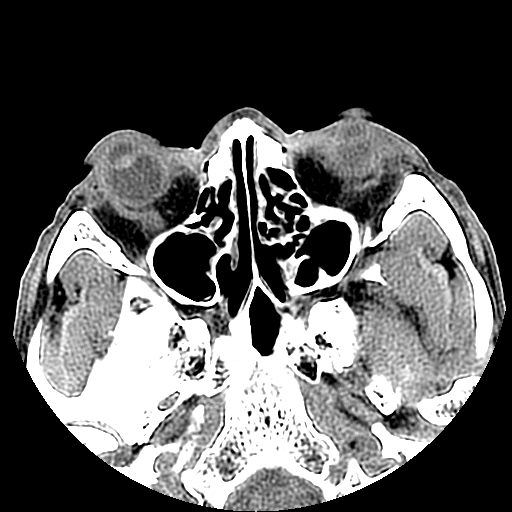

以下是引用liaoqiang在2008-7-16 21:15:00的发言:[br]右侧鼻骨骨折

以下是引用zxd95在2008-7-16 21:39:00的发言:[br]右侧上颌骨额突骨折。[br][br][br][br]